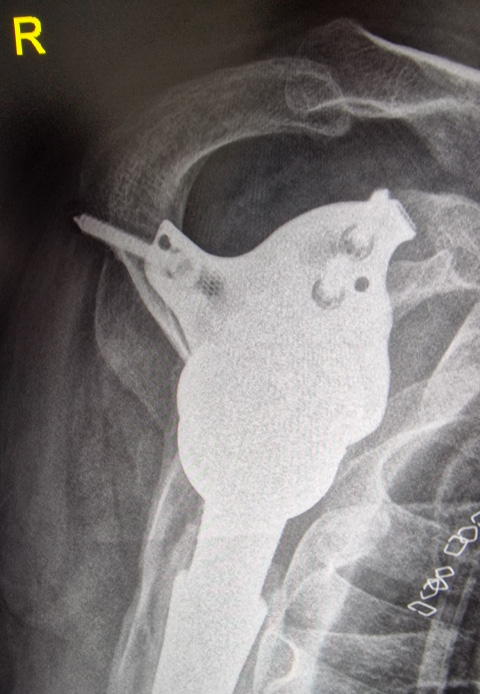

Pre-op

- 49-year-old male

- Height 187 cm / Weight 107 kg

- After three revisions of a right reverse shoulder prosthesis the component got infected with subsequent stem loosening (cemented revision stem)

- Infection treatment with cement spacer

- Target: Reimplantation of cementless RSA with individualized custom-made reverse glenoid baseplate

- CT-Scan image a/p with cement spacer

- Large glenoid defect

- Large humeral bone defect